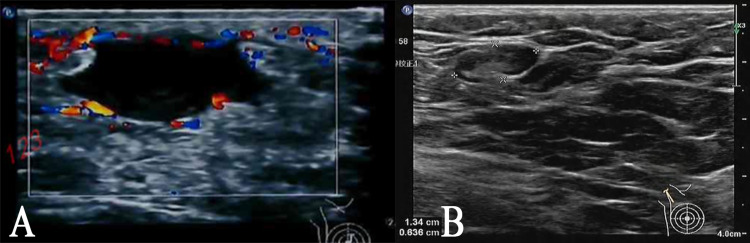

Patient concerns: The male patient presented with a palpable parapapillary mass, erythema, and localized breast pain.

Diagnoses: Radiological and histopathological assessments confirmed the diagnosis of PCM.